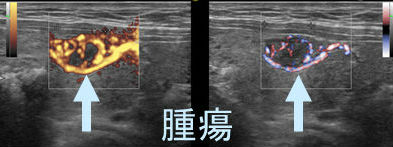

甲状腺腫瘍

甲状腺腫瘍 eFlow(イー フロー)

甲状腺腫瘍[腺腫様結節](拡大)

(左)パワードプラー

(右) eFlow(イー フロー);腫瘍血管が鮮明に

パワードプラーでは、血流信号(カラーの部分)が血管の外にはみ出して血管の走行が正確に分かりません。

eFlow(イー フロー)では、血流信号が血管の外にはみ出さないため、血管の走行が正確に分かります。

甲状腺腫瘍[腺腫様結節] eFlow(イー フロー) 腫瘍血管

甲状腺腫瘍[腺腫様結節]